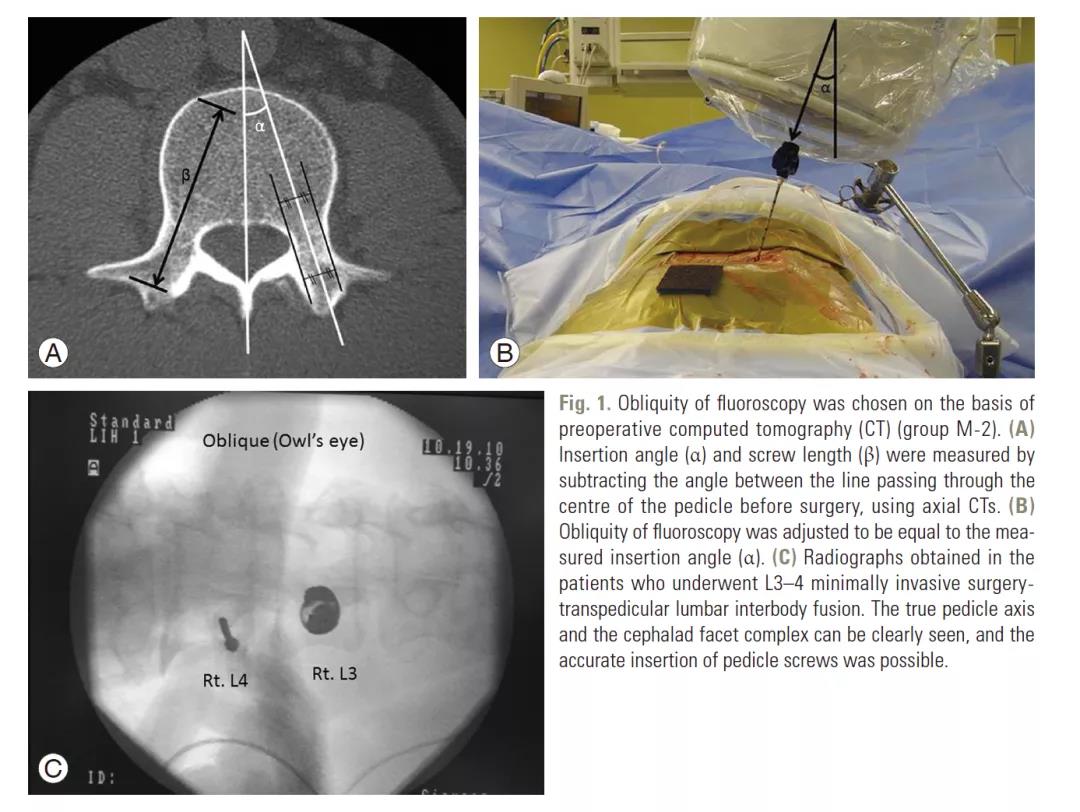

原理:单一斜位其实是椎弓根的轴位,在此位置椎弓根影像成为最大的圆。如果置钉过程中,钉头始终在这个圆内,表明椎弓根钉没有穿破内外上下皮质。方法:①调整C臂头尾倾位置,使终板影重叠成一直线。小技巧,此时C臂头尾倾的角度就是穿刺针头尾倾的角度。②调整C臂内外倾位置,椎弓根圆形影像最大化的位置就是椎弓根的轴位,保持此位置。小技巧,此时C臂内外倾的角度就是穿刺针头内外倾的角度。③进钉点位于圆圈内(最好位于圆中心)。④一直朝圆心方向进入穿刺针,进入椎弓根钉的长度后(腰椎45cm、胸椎35cm、颈椎25cm),透视穿刺针尖没有超过圆圈。⑤另外,掌握了原理后,这种经皮的方法在开放也同样适用。